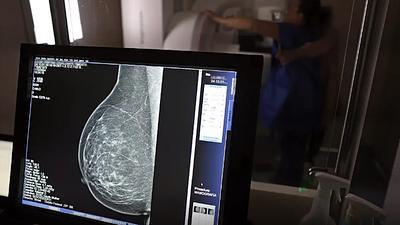

Especialistas reafirmam eficácia da mamografia para prevenir câncer de mama

Os vídeos que circulam na Internet chegam a associar a mamografia ao surgimento de câncer não apenas de mama, mas em outras partes do corpo e também como causa de inflamação e de transtornos de saúde.

Especialista mostra importância da mamografia para prevenir câncer de mama

De acordo com o Inca, a taxa de mortalidade por câncer de mama, ajustada pela população mundial, atingiu 11,84 óbitos por 100 mil mulheres, em 2020, com as maiores taxas registradas no Sudeste e no Sul, da ordem de 12,64 e 12,79 óbitos por 100 mil mulheres, respectivamente.